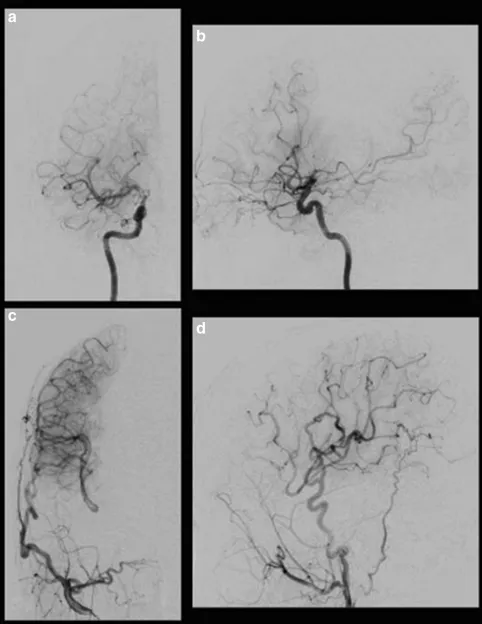

术后即刻在镇静状态下进行Xe-CT检查,以评估高灌注状态。局部高灌注区在搭桥术中被观察到,术后过程非常顺利。病人没有出现癫痫、头痛和新的神经功能缺损等并发症,术后5天和7个月MRI未见缺血性病变。MRA显示STA在7个月内有发展和扩张,选择性右颈外动脉造影显示右侧大脑中动脉区域有大量的血供(图3)。

图3:术后右颈动脉造影显示经右侧大脑外动脉的旁路血流通过MCA和ACA供应到灌注较少的区域。右侧颈内动脉正位(a)、侧位(b);右颈外动脉正位(c)、侧位(d)